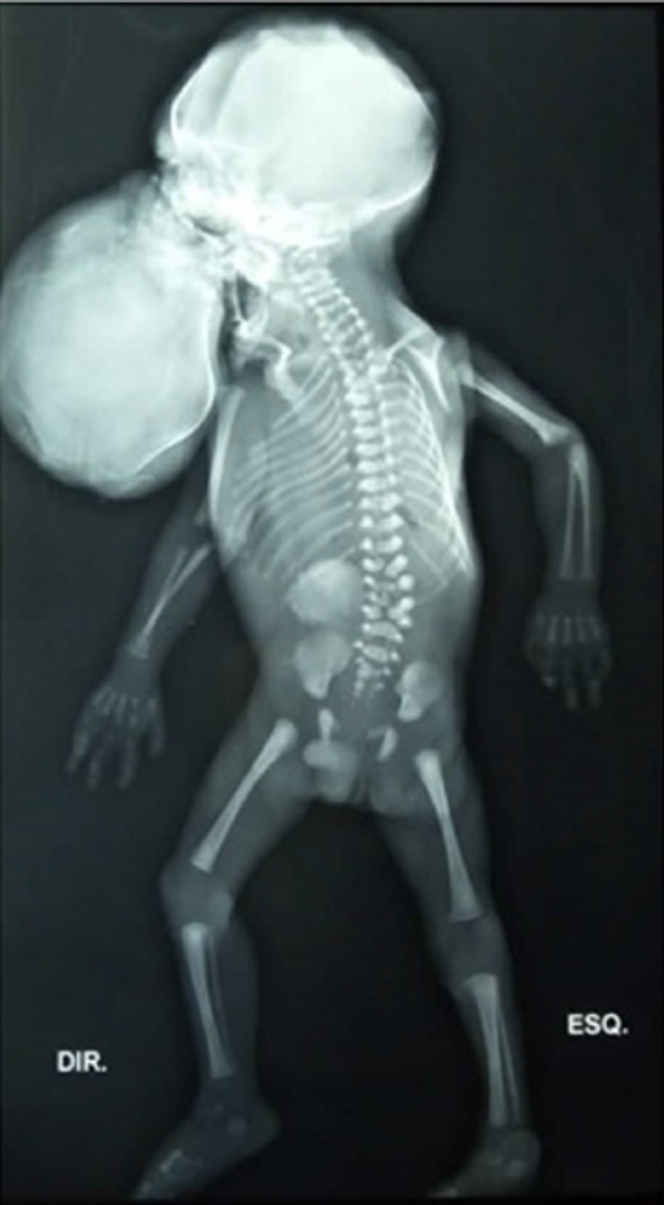

Radiographie du nourrisson mort-né. Une deuxième tête appartenant au fœtus parasite sort de la cavité buccale du fœtus hôte. Le sacrum est absent. Ce cliché correspond au cas exceptionnel relaté à la fin de ce billet.

À 32 semaines et 2 jours de grossesse, lors d’une consultation, les médecins constatent que le cœur du fœtus ne bat plus. La patiente est alors hospitalisée pour déclencher le travail. Le lendemain, elle accouche par voie basse d’un garçon mort-né pesant 1,5 kg. À la radiographie, les médecins constatent qu’il présente une agénésie du sacrum, c’est-à-dire une absence totale de cette structure osseuse située à la partie inférieure de la colonne vertébrale.

L’examen externe du fœtus parasite révèle alors une scène saisissante : une tête, entièrement recouverte de peau, émerge de la bouche du fœtus, reliée à lui par un large pédicule.

L’autopsie confirme qu’il ne s’agit pas d’un tératome épignathe (tumeur bénigne sortant de la bouche), mais d’un fœtus in fœtu siégeant dans la cavité buccale.

Une deuxième tête émerge de la bouche du jumeau hôte

Cette structure fœtiforme, qui mesure 10 × 7 cm, comporte des cheveux, des os crâniens, des traits faciaux (deux fentes palpébrales bordées de cils, une structure ressemblant à un nez, une partie de la lèvre supérieure, mais pas d’yeux).

À la dissection, cette « tête parasite » présente deux hémisphères cérébraux peu développés et une hydrocéphalie (augmentation du volume des ventricules contenant le liquide cérébrospinal). Surtout, le cerveau n’est pas relié anatomiquement à la colonne vertébrale du fœtus hôte.